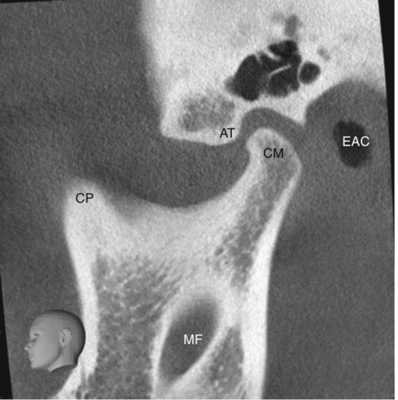

Рисунок 4 Сагиттальный срез конусно-лучевой компьютерной томографии височно-нижнечелюстного сустава у 22-летней женщины. АТ Суставной бугорок, СМ мыщелок нижней челюсти, СР венечный отросток, ЕАС наружный слуховой проход, МF отверстие нижней челюсти